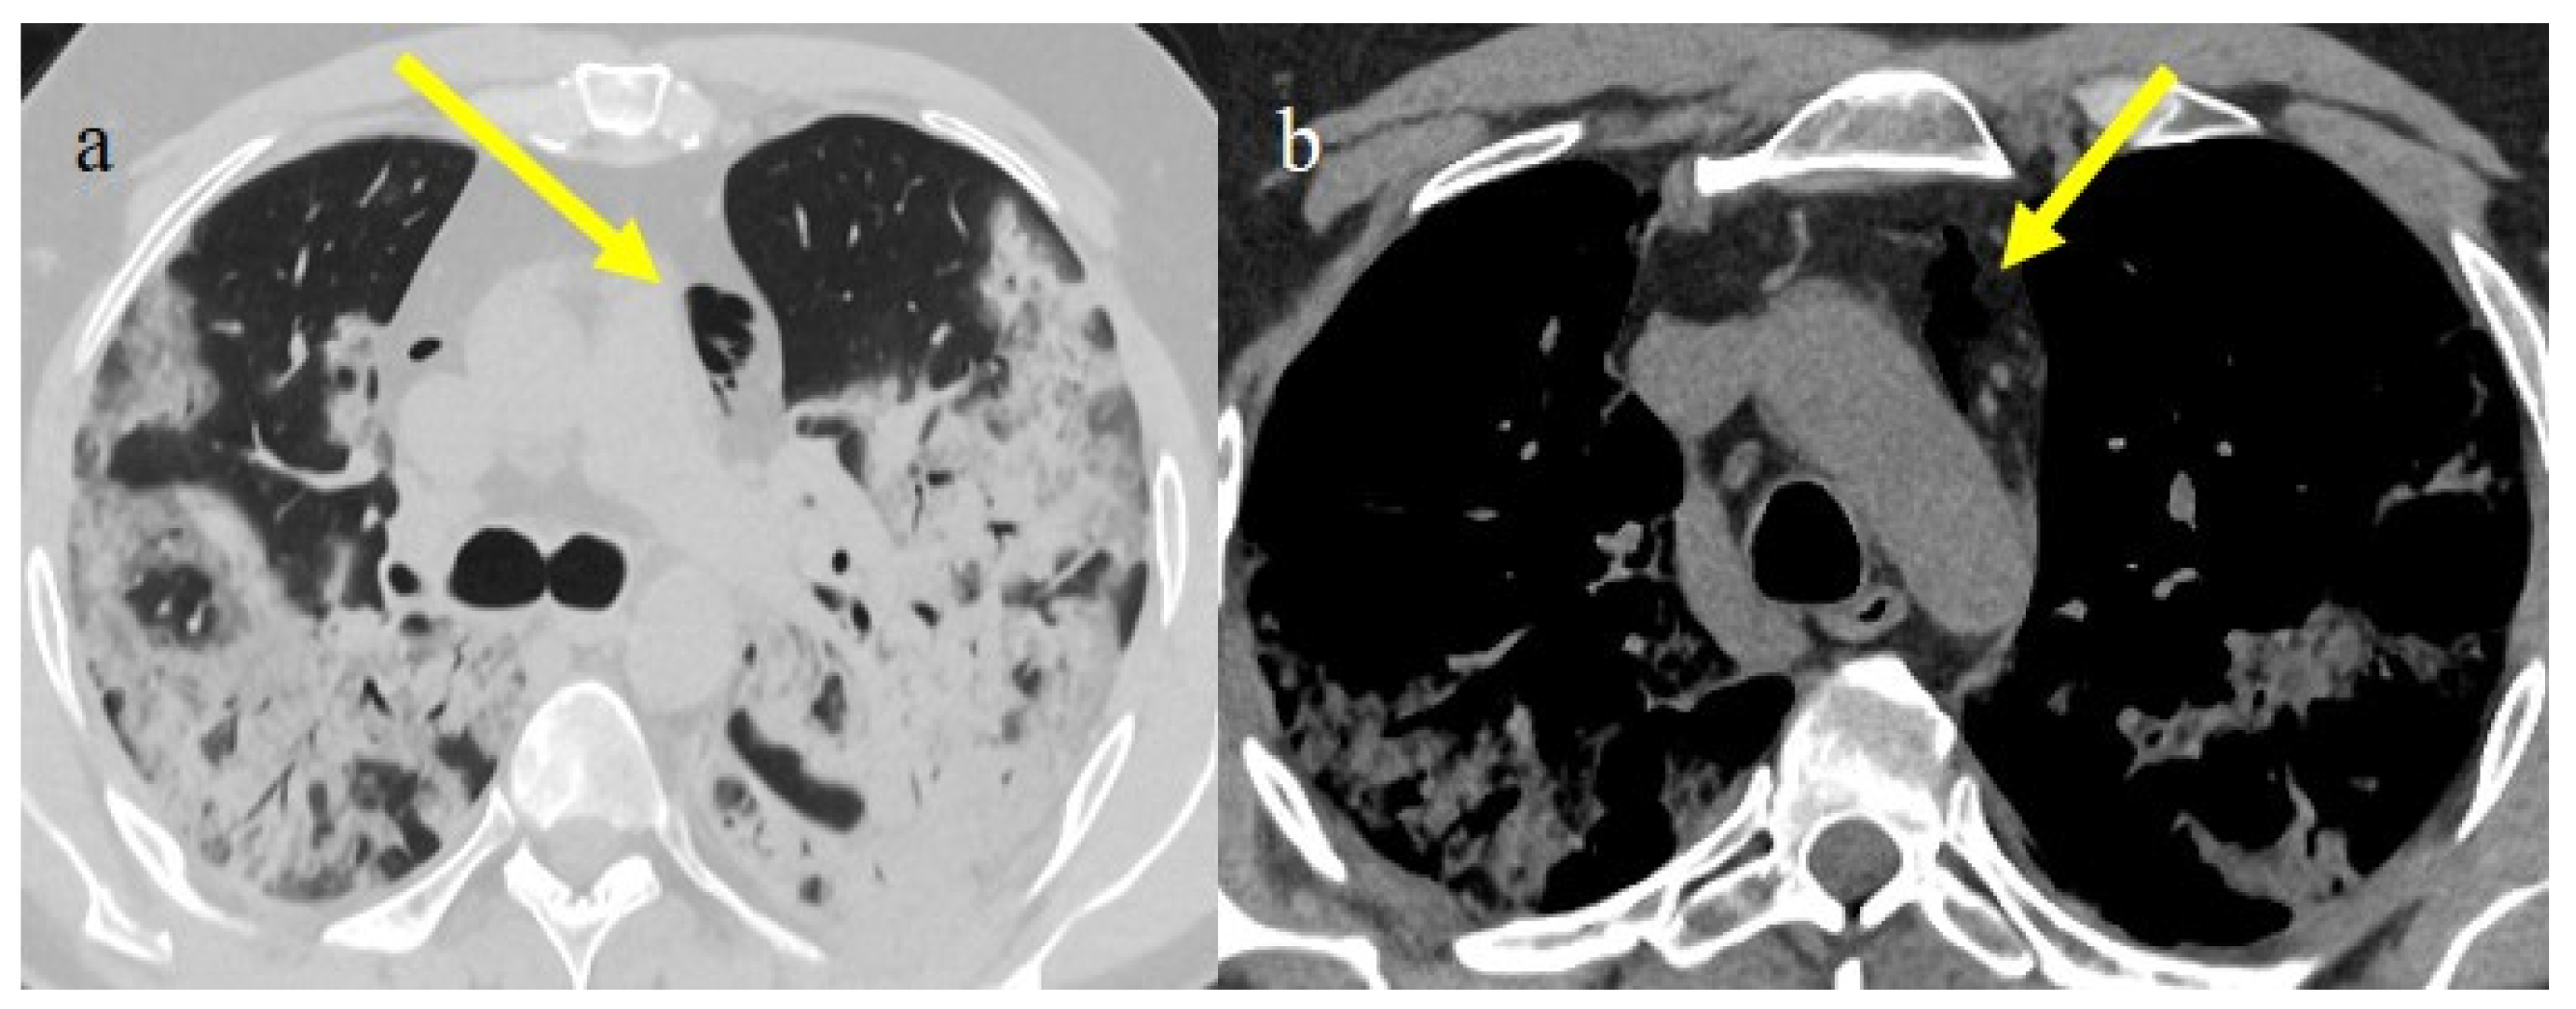

The differential diagnosis of COVID-19 pneumonia includes other infective forms of pneumonia such as bacterial pneumonia (usually lobar consolidation) and atypical pneumonia (multifocal distribution with centrilobular nodules), other viral forms of pneumonia, and cardiovascular pathologies such as pulmonary edema [62] (Figure 3 and Table 1).

Figure 3.

In this figure some differential diagnosis of COVID-19 pneumonia with atypical features are shown; in image (a), a solitary segmental bronchopneumonia is seen; image (b) shows an atypical bacteria pneumonia with consolidation areas and centrolobular nodules in a patient with immunosuppression state with positivity on BAL of Escherichia coli; image (c) illustrates an atypical pneumonia with multiple consolidations and centrolobular nodules in a patients with syncytial respiratory virus infection; image (d) shows consolidations with central hilar distribution ad bilateral pleural effusion with pulmonary edema.

It is usually possible to differentiate COVID-19 pneumonia from other viral pneumonia, such as that of influenza or syncytial and parainfluenza viruses and other coronaviruses, with a CT scan [63,64,65]. The diagnostic accuracy usually increases with the use of deep learning [66]. The resulting CT features that have been reported as the most strongly associated with COVID-19 pneumonia are the subpleural band of GGOs, where thickening of the bronchial walls and micronodules are usually more frequently associated with other viral pneumonia [63,64,65] (Figure 3c). However, some CT findings may overlap between COVID-19 pneumonia in influenza pneumonia [65]. Both COVID-19 and influenza pneumonia could show a diffused distribution; however, a lower-lobe-predominant distribution was reported to be more common in COVID-19, and an upper-lung-predominant distribution is slightly more common in influenza [65].